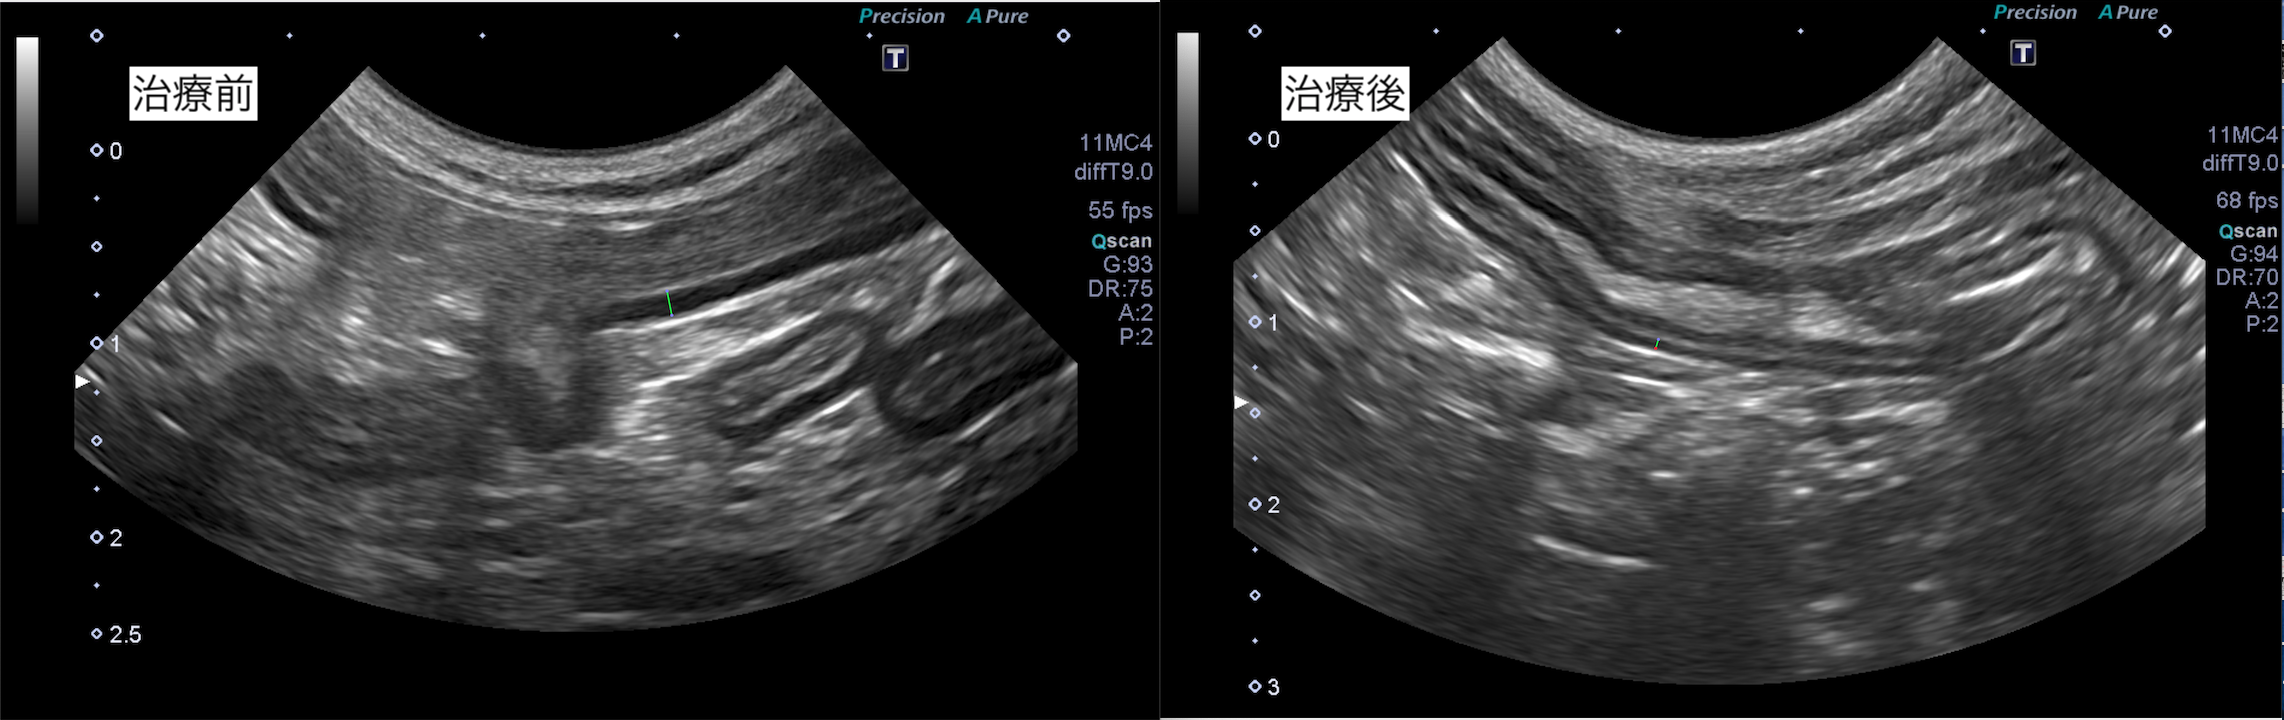

超音波検査で消化管の異常を把握することは可能ですが、内視鏡検査や開腹での生検を行わないと確定診断は行えません。

超音波検査では、消化管の構造の一部肥厚が認められました。

本症例はステロイドの内服を開始したところ、症状が改善しました。

また超音波検査でも粘膜の肥厚は改善傾向です。